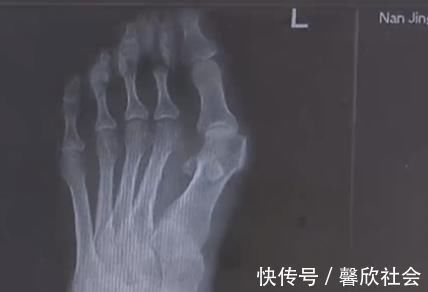

穿高跟鞋是不少女生出门前的必备,今年32岁的王女士十几年前就有了穿高跟鞋的习惯。然而就在最近,自己的脚趾出现了惊人的变化,两边的大脚趾一侧渐渐突起了一个硬疙瘩,走路一久就疼痛不已。

由于高跟鞋的挤压,王女士的左脚大脚趾变成了两个脚趾,随着时间的推移,大脚趾一侧又多了一个 \\\\'\\\\'拐\\\\'\\\\',现在只能通过手术来缓解症状。除了鞋子不当,遗传和疾病因素也是造成拇指外翻的原因,70 岁的高女士患风湿病,脚也发生了接近 60 度的严重变形。